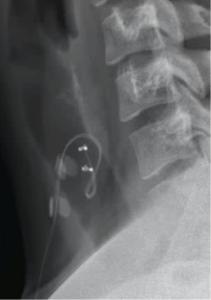

In Vagal Nerve Stimulation (VNS), electrical therapy is used to alter neural circuits in the brain which in turn reduce the chance of seizures. Other benefits include reducing medications, reducing seizure duration and severity, and improving mood. To do this, a device is surgically implanted. This comprises a lead with coils that wrap around the vagus nerve in the neck, and a battery which sits just under the collar bone.

These days, this is a routine day-case procedure. However, it requires close follow-up and programming, with the benefit tending to steadily improve over time.